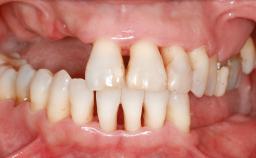

Guided Bone Regeneration (GBR) with a Particulated Autologous Graft and a ePTFE-Reinforced Membrane for Vertical Augmentation of a Single-Tooth Edentulous Space in the Esthetic Zone

A 47-year-old Caucasian woman with a single-tooth edentulous space at the site of the left maxillary canine was referred for treatment. She had undergone traumatic extraction of this impacted canine several months before referral. Her chief complaint was the dissatisfying appearance of her smile. The patient desired a stable and esthetic rehabilitation of the site. Her dental history showed no evidence of periodontal disease or bruxism. She had no systemic diseases, was not taking any medications, and did not smoke. The extraoral examination revealed a high lip line and an inadequate soft-tissue volume at the defective canine site. Large black triangles were visible between the canine and its adjacent teeth.

Lip Line No exposure of papillae Exposure of papillae Full exposure of mucosa margin

Soft Tissue Anatomy Intact Defective